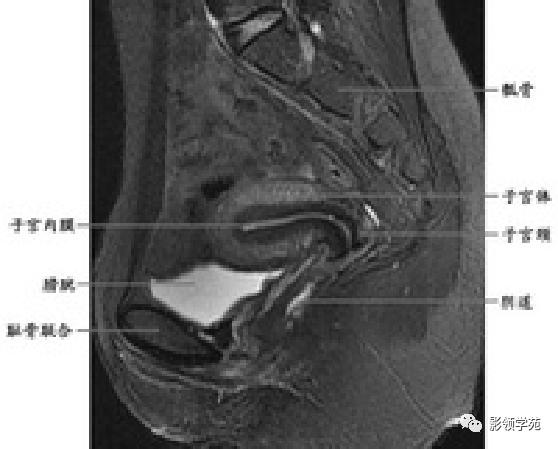

T1WI:呈均匀低信号,周围为高信号脂肪

T2WI : 宫体三层:

中心高信号---子宫内膜和分泌物;

中间低信号带---子宫肌内层,亦称结合带;

周围呈中等信号---子宫肌外层

T2WI :

宫颈四层:

高信号---宫颈管黏液

稍高信号---宫颈黏膜皱襞;

低信号---宫颈纤维基质(与宫体JZ连续)

等信号---宫颈肌层

宫颈

T1WI表现为较均匀一致的稍低信号

高分辨率T2WI可看到4层结构

最内层-高信号粘液

粘膜层(柱状上皮)-高信号,低于粘液信号

纤维间质(结合带)-低信号

肌层-中等信号